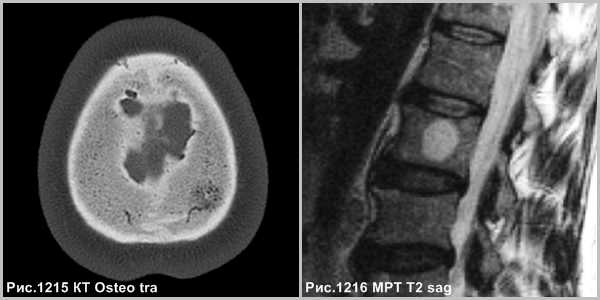

Очаговое изменение в диплоическом веществе свода черепа (рис.1215) и очаг в толще губчатого вещества тела позвоночника (рис.1216), состоящее из кавернозных полостей.

Морфологически различают первичную внутрикостную гемангиому и гемангиомы мягких тканей, вторично поражающих кости черепа (гемангиоматоз). Первичные внутрикостные гемангиомы растут медленно, как правило, расположены в губчатой кости. В большинстве они доброкачественные, но редко могут быть локально агрессивными. На КТ определяется рассасывание губчатого вещества с наличием радиальных костных балок. Гемангиома медленно растет (5-6лет), иногда самопроизвольно прекращает рост, сопровождаясь жировой инволюцией.

Гемангиома в плоских костях черепа - не частое образование, которое располагается преимущественно в диплоическом слое. Имеется разряженное строение губчатого вещества и толстые костные трабекулы, радиально расходящиеся в стороны. Очаг разряжения губчатого вещества в толще диплоического слоя определяется как зона↓плотности на КТ (стрелка на рис.1221) и↑МР-сигнала на Т2 и Flair (головки стрелок на рис.1219-1221).